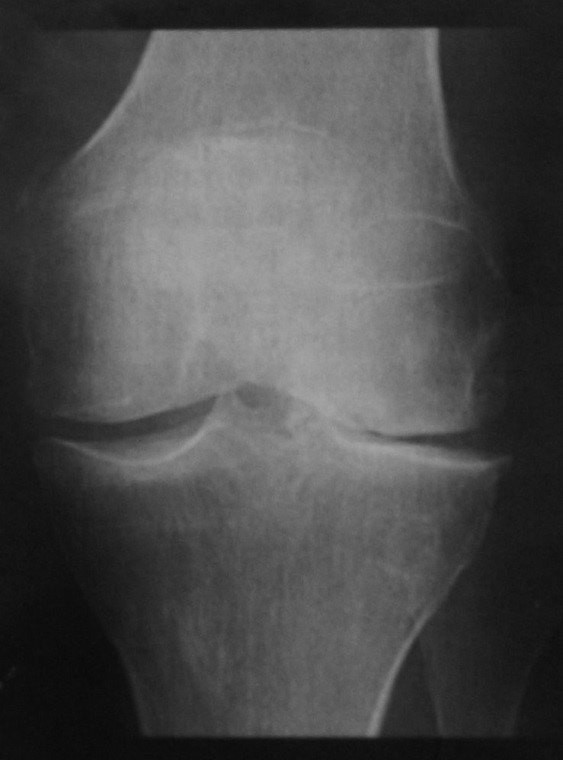

Преимущественно латеральный бедренно-большеберцовый остеоартрит. Рентгенологическое исследование коленного сустава в прямой проекции демонстрирует сужение суставной щели, субхондральный склероз, центральные и периферические остеофиты. Хондрокальциноз определяется как кальцинаты в месте прикрепления медиальной коллатеральной связки после разрыва, возникшего несколько лет назад.

Остеофиты на рентгенограмме и на МРТ выявляли как краевые приострения суставных поверхностей костей(рис.1). Остеофиты на рентгенограмме были выявлены в медиальном и латеральном отделах в 40(59.7 %), на МРТ в 67(100 %) и 57(85 %) суставах соответственно.

На рентгенограммах субхондральный склероз выявляли как участок повышения плотности (рис.1). На МРТ участки субхондрального склероза определяются как зоны понижения интенсивности сигнала костного мозга. Субхондральный склероз на рентгеногамме в медиальном отделе выявлен в 40(59.7 %), в латеральном отделе в 10(14.9 %), на МРТ в 30(44.7 %) и 8(11.9 %) суставах соответственно.

Рис. 1. Рентгенограмма и МРТ коленных суставов больной З.,62 лет. На рентгенограмме (А) выраженное сужение медиальных отделов суставной щели, краевые остеофиты, субхондральный склероз. На МРТ(Б) краевые приострения, выраженные дегегнеративные изменения в медиальных отделов субхондральной кости, выраженное истончение медиального отдела хряща. Дегенерация медиального мениска

Остеоартроз характеризуется следуюшими патологическими изменениями: истончение гиалинового хряща, склероз и образование кист в субхондральных отделах костей, остеофиты (см.рис.1) [1,3,4,9]. Рентгенография используется как первичный метод выявления и мониторинга остеоартроза коленного сустава.